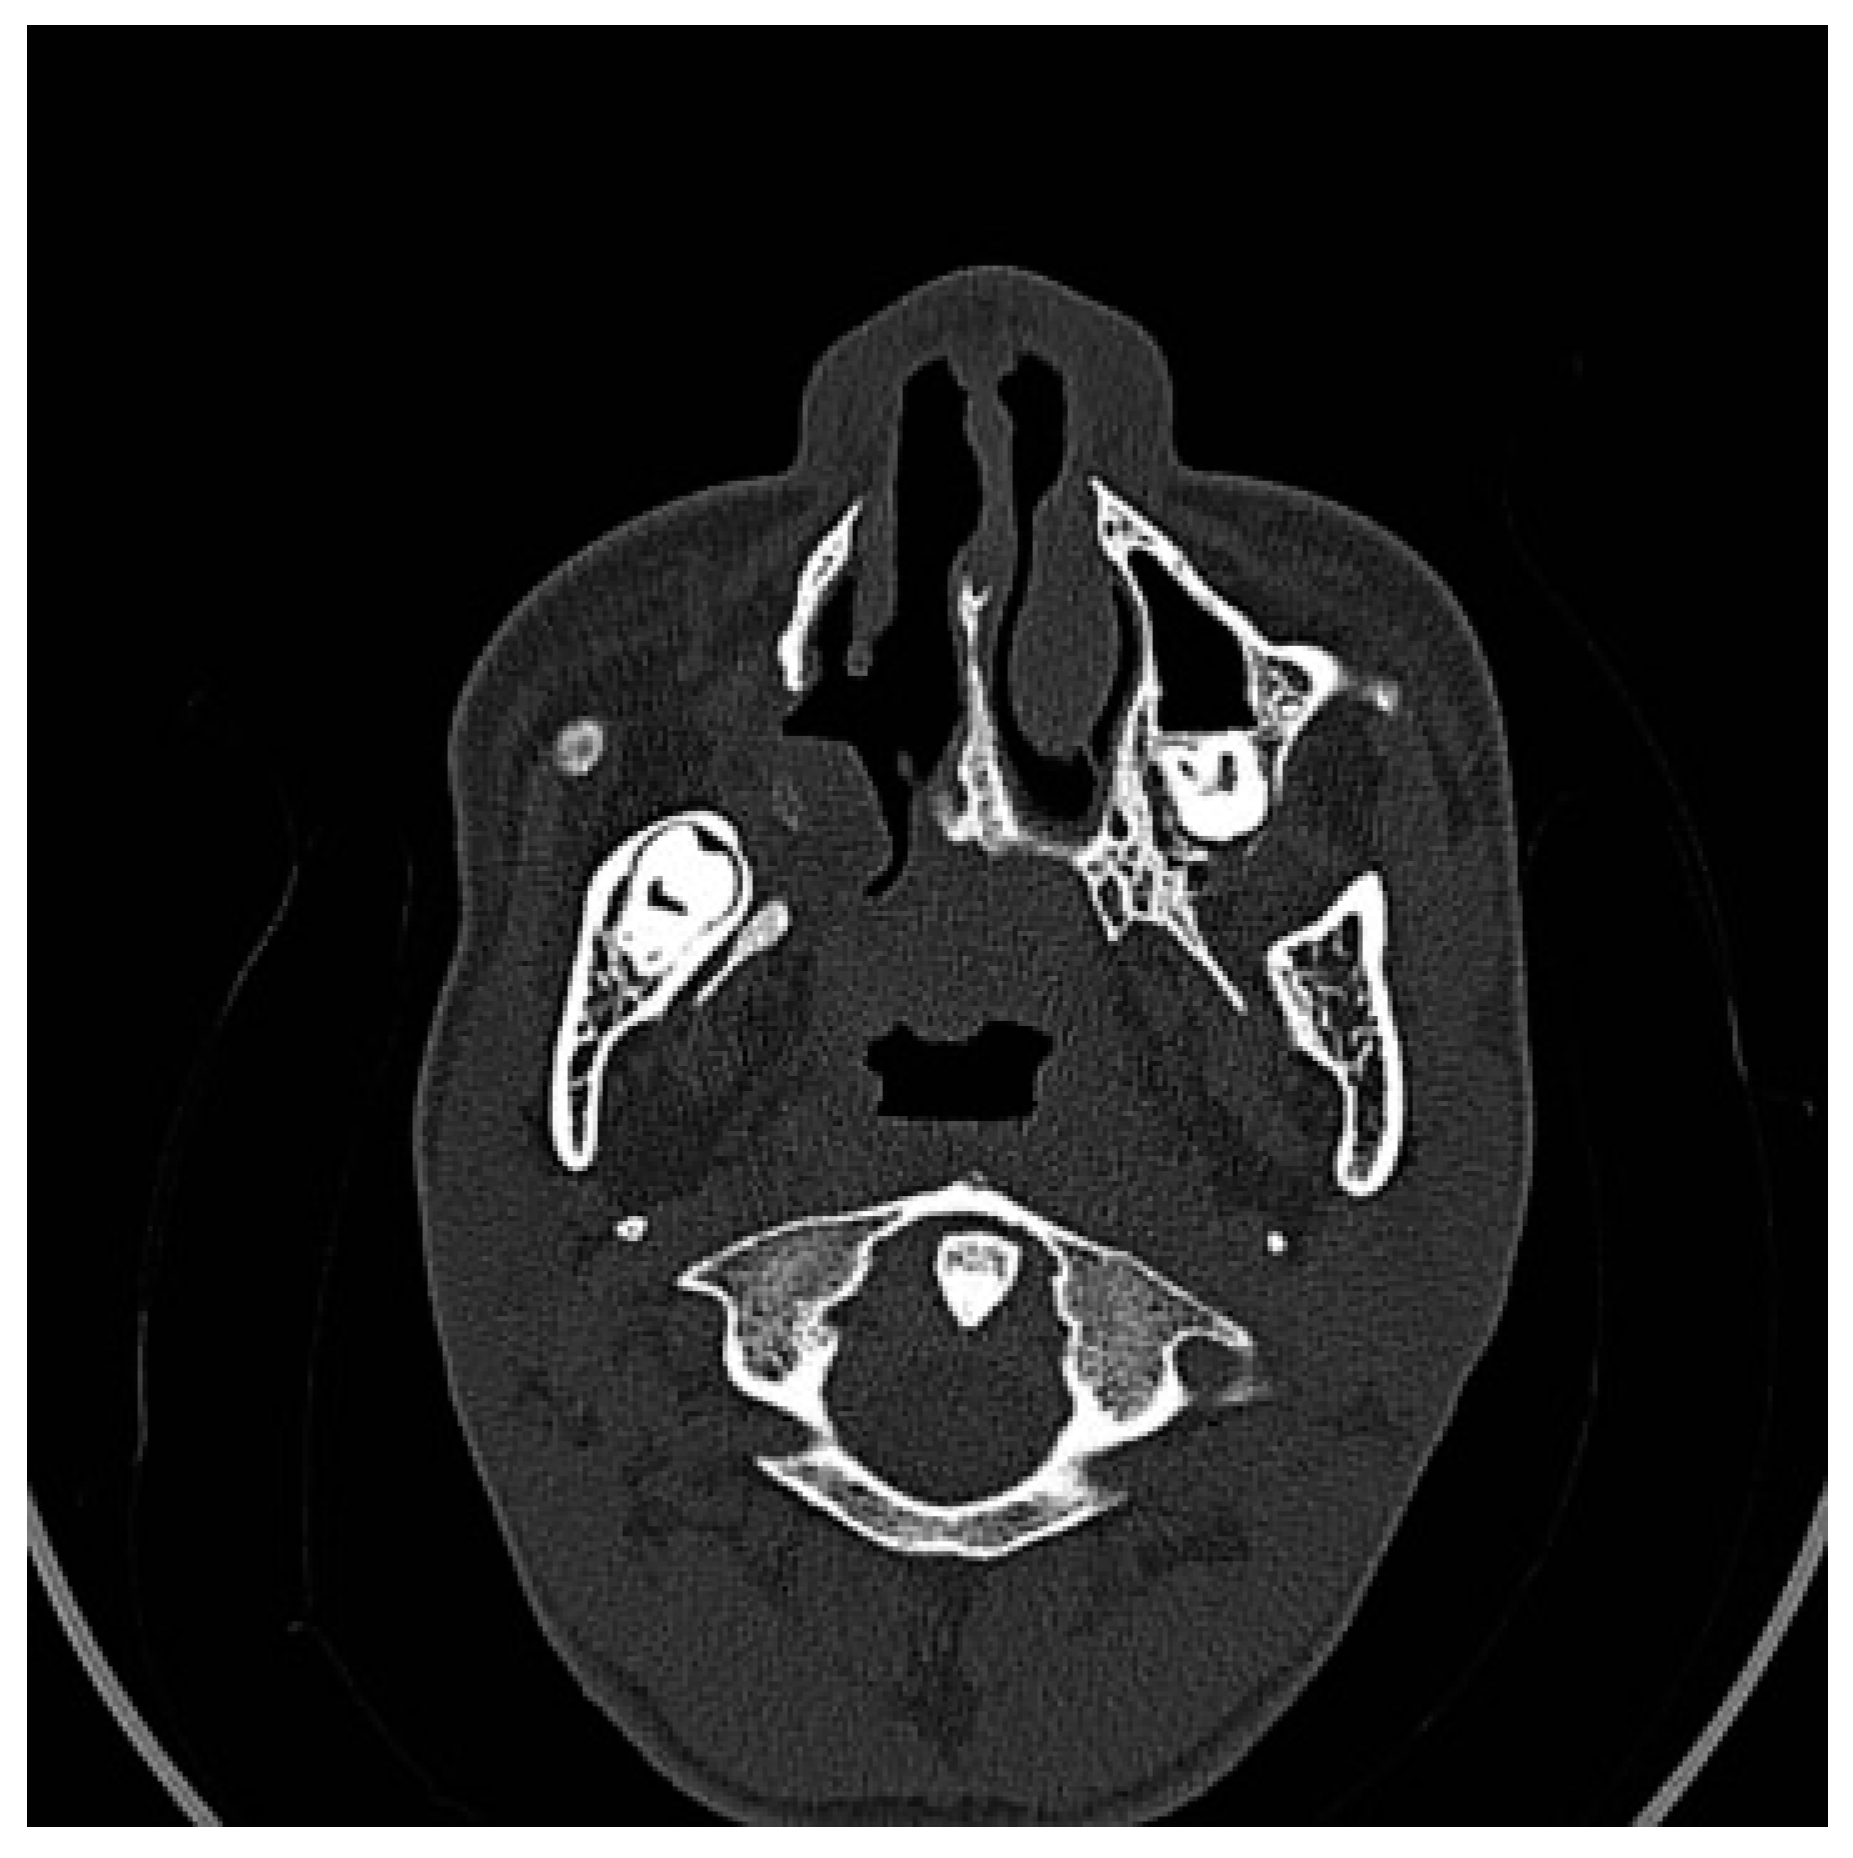

Figure 2. Preoperative CT scan. Axial view: agenesis of the right turbinate and cleft palate.

A CT scan of the head with 3D reconstruction (Figure 1, Figure 2, Figure 3, Figure 4 and Figure 5) confirmed a maxillomandibular fusion associated with a cleft palate, agenesis of the right turbinate, and right hemifacial microsomia (Laster type 2b syngnathia). Both temporomandibular joints (TMJs) were normal and showed no bony ankylosis (fibrous ankylosis could not be excluded with the given data).